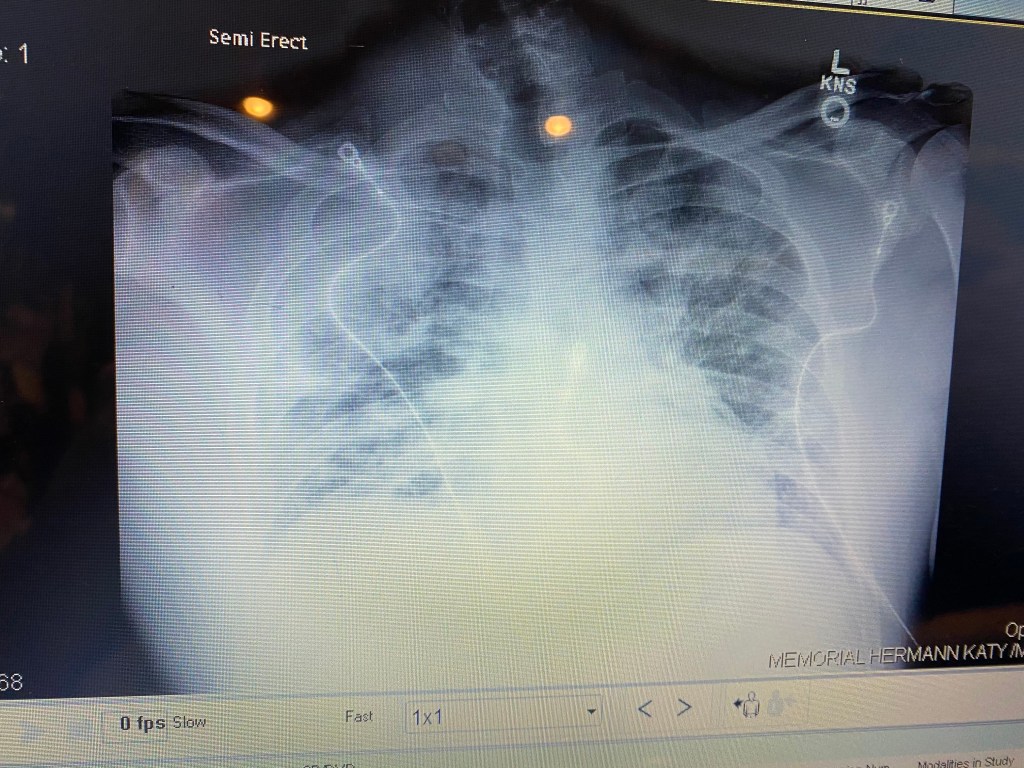

After my oxygen saturation stabilized and I was able to lay on my side, I started to develop a pretty serious cough around February 11. My sternum was bruised significantly from laying on my stomach and coughing for so long and it took me three or four days to really sort through that pain. By the end of the week around the 13th or 14th, my lungs showed significant improvement. I was set to be discharged the next day, but as these things seem to go, I started to run a fever again on the 14th and it turned out that I contracted something new. My fever started pushing 103 degrees and blood tests showed that my white blood cell count was very elevated and my kidneys were functioning at 50 percent. I contracted bacterial pneumonia and my immune system was turning on me.

And so the battery of chest x-rays and blood tests commenced again. The veins in my arms were already destroyed. It took them over 12 tries to hit a vein one time because they had already exhausted both of my hands, forearms, elbows and the top sides of my arms. I estimate that during the time I spent in the hospital, my arms were stuck over 200 times, with more than seven IVs put in me because a few of them blew through and others just got old and had to be replaced.